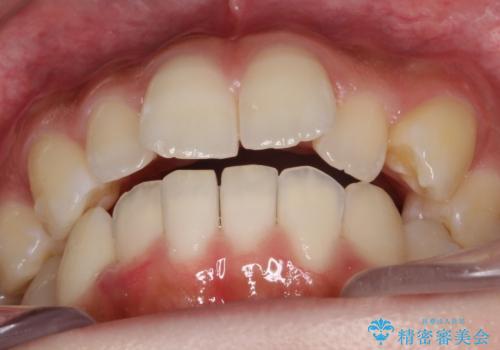

- 前歯の歯並びの改善を希望され来院された患者様です。

初診時の歯並びの状態としては、上下ともに全体に及ぶの中等度のがたつき(叢生)があり、全特に左上の前歯は1本だけ引っ込んでいる状態でした。

抜歯は行わず上顎の奥のスペースを利用して歯をスライドする方法の他に歯列弓の拡大やディスキング(歯と歯の間の隙間を作る処置)を行い叢生を改善しました。

歯の大きさの不揃いが原因の正中のズレは、ディスキング量を調整することで合わせています。

上の歯を後ろに送る方法として、歯茎に入れた小さなネジからゴムかけをして歯列全体を後ろに引っ張りました。